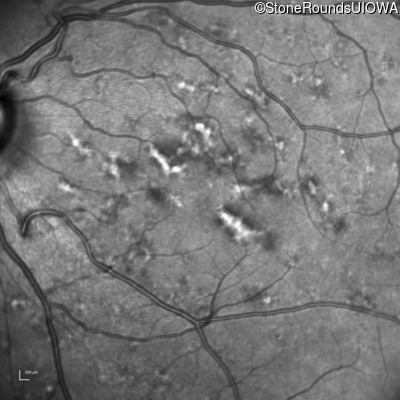

Visit at age: 40 years

Blue Autofluorescence - Right - 20/20 -2

Exemplar